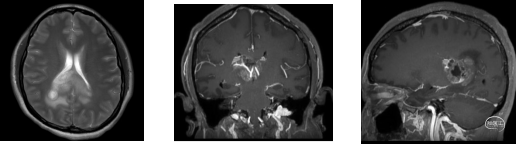

术前MRI

锥体束及视辐射

临床症状进行性加重,短期内出现头痛症状,影像学提示胼胝体压部占位,肿瘤紧邻三脑室顶后部、中脑顶盖、中脑导水管、四叠体池/脑深部引流静脉受压明显,占位效应重。

手术风险评估:肿瘤位于脑中央深部,毗邻重要功能结构,与大脑内静脉、大脑大静脉、脉络膜后内侧动脉、中脑顶盖关系密切,肿瘤血管丰富,可能来源于脉络膜动脉及其分支。

本例患者影像学上表现为累及胼胝体压部的典型的蝴蝶状胶质瘤,病变累及双侧半球,非对称分布。手术均用右侧顶枕叶造瘘+左侧纵裂入路,术中先后探查和分块切除大脑镰后部两侧的病变。大脑镰后部毗邻大脑深部静脉系统,需要尽可能避免损伤Galen静脉或下矢状窦等重要结构,左侧纵裂入路可能有利于实现更好的功能保护。位于胼胝体不同部位的蝴蝶状肿瘤,由于解剖基础和功能保护的需求,采取不同的入路,从而在尽可能保护脑功能的前提下安全切除病变。